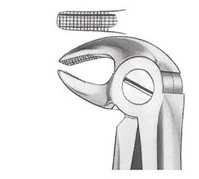

Aby przeprowadzić ekstrakcję zęba oznaczonego numerem 13 w systemie uniwersalnym, jakie kleszcze należy przygotować?

Które kleszcze są używane do usuwania korzeni górnych?